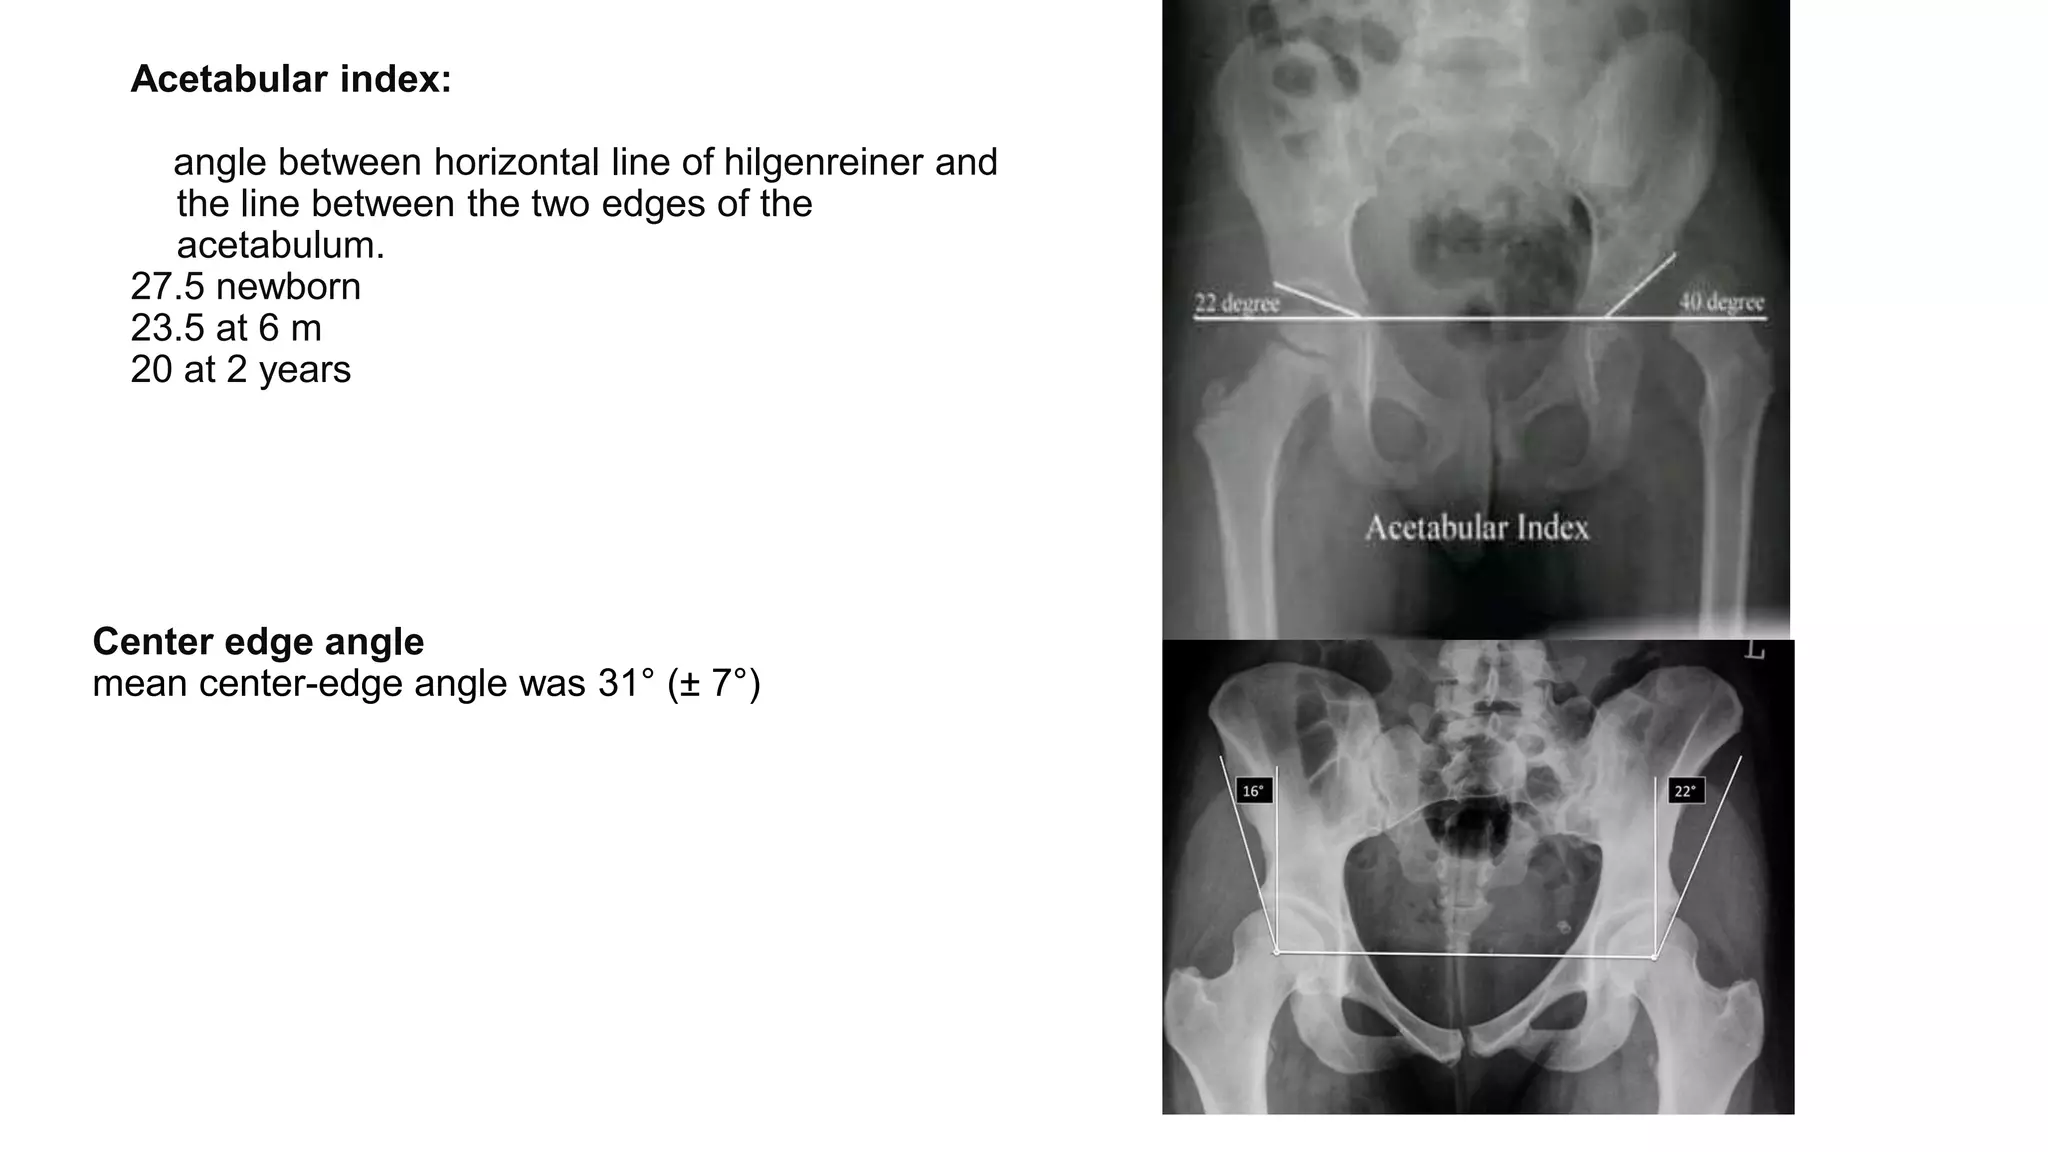

Acetabular index:

angle between horizontal line of hilgenreiner and

the line between the two edges of the

acetabulum.

27.5 newborn

23.5 at 6 m

20 at 2 years

Center edge angle

mean center-edge angle was 31° (± 7°)